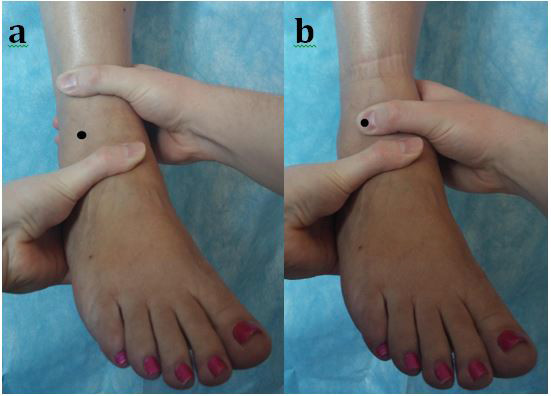

L’ADT est réalisé en fixant la partie distale du segment jambier et en appliquant une force de translation antérieure sur le talon avec l'autre main, comme illustré à la figure 2A.

Le MADT repose sur la même position, mais le pouce de la main tenant le tibia est placé sur la face antéro-latérale du talus pour immobiliser l'articulation tibio-talienne, comme le montre la figure 2B.

Fig 2

Il en résulte que le talus et le tibia deviennent une seule unité et annulent la traduction antérieure du talus du tibia. Tout mouvement se fait donc à partir de l'articulation sous-talienne seule, isolant ainsi la translation antérieure de la tibio-talienne.